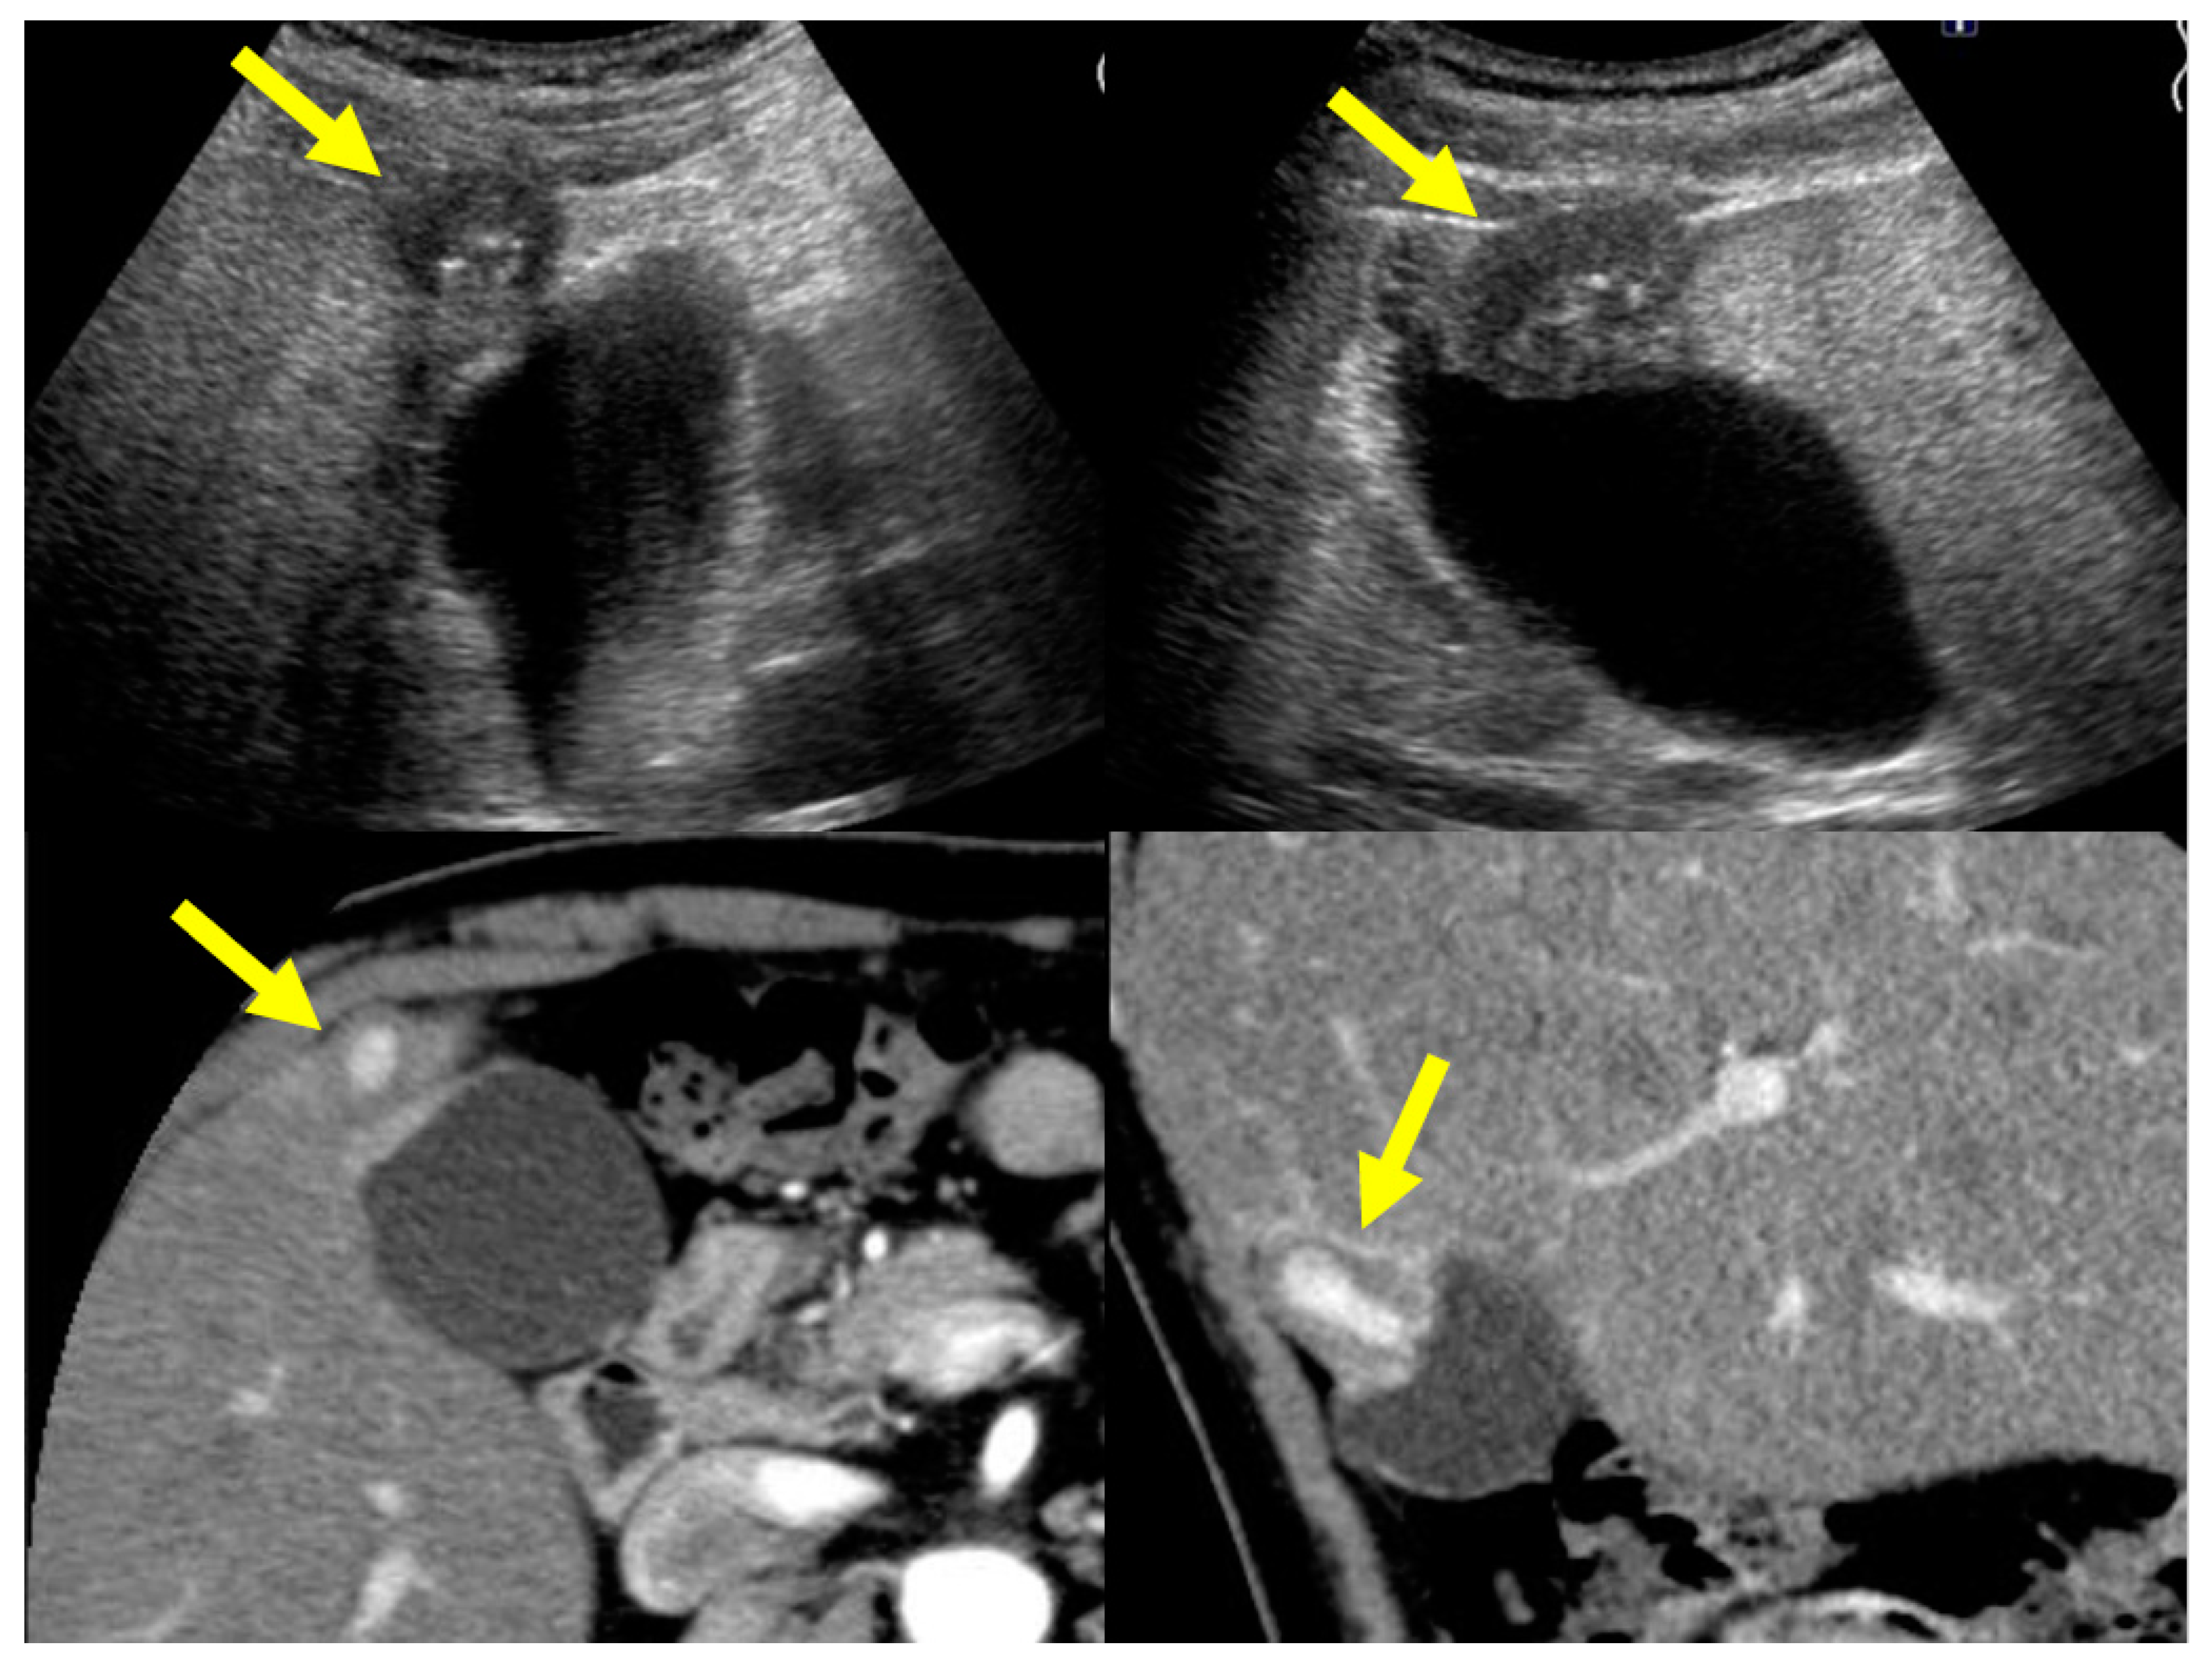

4.1. Diffuse Type of IgG4-CC

4.2. Localized Type of IgG4-CC

5.1. Gallbladder Cancer

5.2. Adenomyomatosis